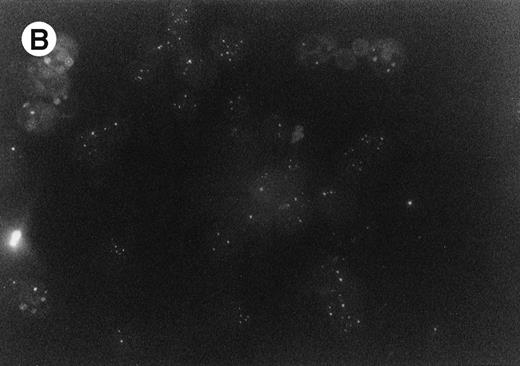

Leukemic blasts of the patients were labeled with fluorescent antibodies (Abs) specific for RARα, RXRα, and PML.5Leukemic cells of both cases displayed cytoplasmatic perinuclear reactivity with anti-RARα (Fig 1A); this reactivity was apparent as small granulations forming a ring around the nucleus of the cells. In contrast, labeling of the cells with RXRα and PML Abs displayed the typical nuclear reactivity, the former under form of diffuse nuclear staining and the latter under form of the nuclear bodies staining (Fig 1B). Several controls were performed in normal hematopoietic cells or in leukemic non-APL cell lines to verify the specificity of the staining obtained with anti-RARα antibody. Specifically, in HL-60 cells and in normal myeloid and in several (30) cases of primary AML (excluding M3), the antibody gives rise to the expected nuclear reactivity. Western blotting analysis of RARα performed on cellular lysates derived from the leukemic blasts of the 2 patients displayed a major band with an apparent molecular weight slighly lower than the 2 RARα bands observed in cell lysates derived from controls (Fig 2). This observation was confirmed on several occasions Southern blotting analysis with different restriction enzymes performed under conditions appropriate either for detection of RARα gene rearrangement observed in PML-RARα+ APL or of PML-RARα mRNA failed to detect a gross deletion of rearrangement of the RARα gene (data not shown). Furthermore, several different regions of the RAR-α mRNA have been amplified, reverse transcribed, and sequenced and no abnormalities were observed (data not shown).

RARα (A) and PML (B) immunofluorescence labeling of bone marrow cells derived from one of the two patients.

The impressive therapeutic results obtained in promyelocytic leukemia encouraged the exploration of the RA therapy in patients with different forms of leukemia. In this context, some studies have been performed on relapsed and refractory or poor prognosis AMLs, in which RA was used along with either standard or low-dose Ara-C; in these studies, a variable, but significant proportion of the patients exhibited a therapeutic response to treatment.3,4 However, in these studies, the pattern of RARα expression as well as the integrity of RARα alleles were not investigated. Neither of our patients exhibited morphological, cytogenetic, or molecular abnormality, suggesting an APL or APL variant. However, investigation of the cellular localization of RARα by immunofluorescence showed an aberrant protein distribution, altering expression from the nucleus to the cytoplasm. Of interest, both APL and these 2 cases of secondary AML exhibit an abnormal pattern of nuclear protein localization (PML and RARα in APL and only RARα in secondary leukemias) that may be used for rapid diagnosis. However, an interesting difference between APL and the 2 secondary AMLs of the present study consists in the relocalization of both PML and RARα after RA treatment observed in APL,6 as compared with the permanently delocalized cytoplasmatic pattern in secondary AML after RA treatment. It remains to be determined whether the delocalization of RARα protein from the nucleus to the cytoplasm observed in these 2 patients is dependent on an alteration of 1 of the 2 RARα alleles. In this context, Western blot analysis of cell lysates showed, with a specific anti-RARα antiserum, the presence in both patients of an RARα protein exhibiting a slightly reduced apparent molecular weight. This alteration could be dependent either on a mutation in the coding sequence of 1 of the 2 RARα alleles or on a posttraslational modification. In conclusion, our study indicates that secondary AML can be responsive to differentiating therapy with ATRA; these leukemias are characterized by an anomalous RARα subcellular localization.